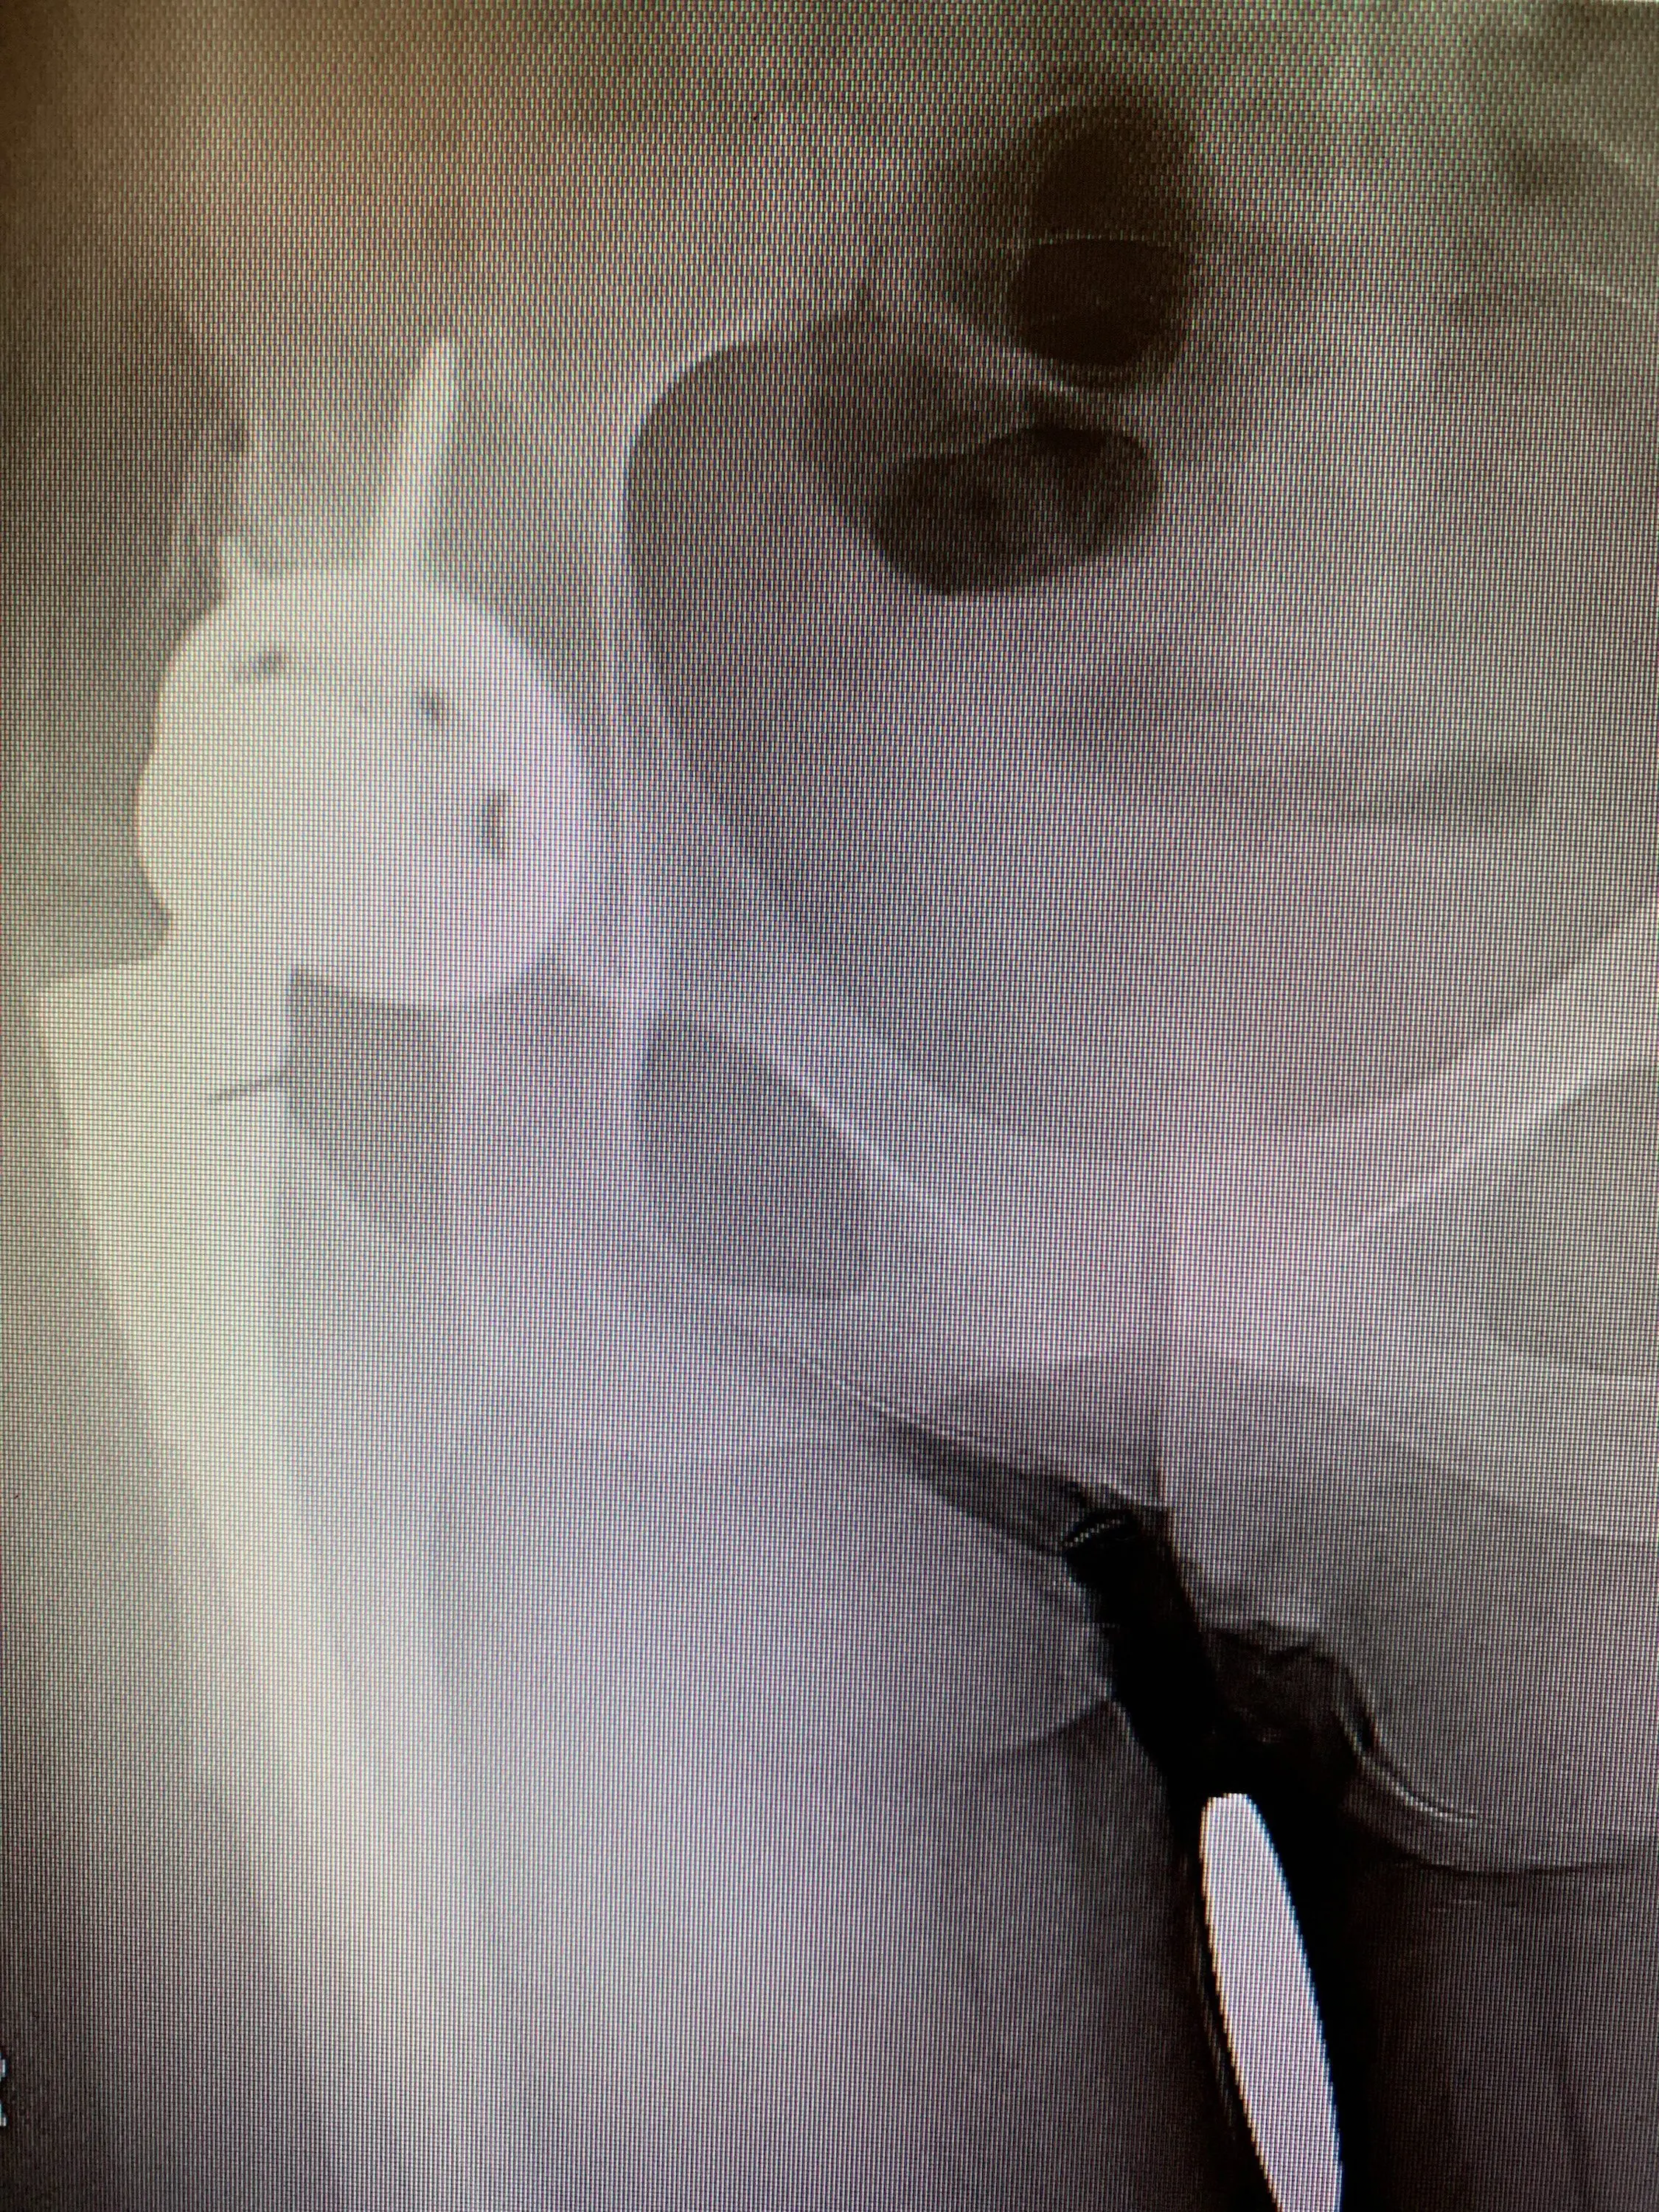

She is a non-smoker. We performed the revision surgery through a lateral approach – the approach used for her initial hip replacement. We exposed her artificial hip fully, and removed her acetabular component only.

Our plan was to exchange this component for an alternative that facilitated a dual-mobility construct – one that has proven to address the problem of instability very well.

Pre-op

Post-op